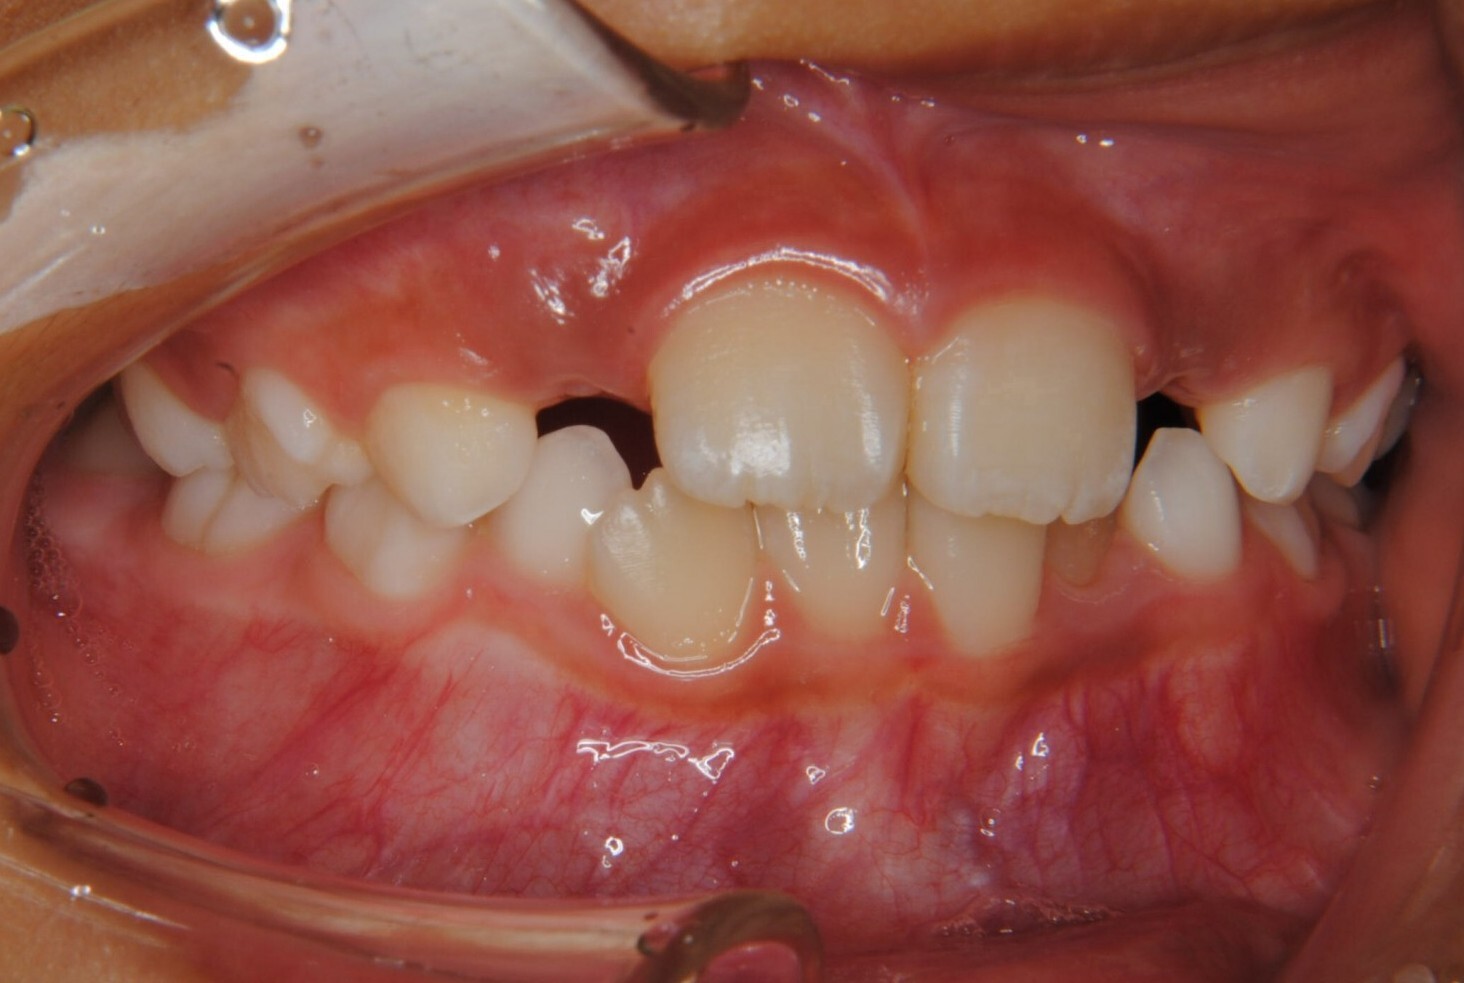

①主訴:下の前歯のデコボコ

②診断名:Ⅰ級叢生

③年齢:初診時(左写真)8歳6か月、終了時(右写真)11歳4か月

⑧リスクと副作用:特に大きなリスクや副作用はありませんでした。拡大床装着直後は違和感があったようですが、特に痛みを感じることなく6.5mmまで拡大できました。その後永久歯への生え変わりも順調で、ほぼ正常な咬み合わせになりました。この後11歳4か月まで観察し、7番目の奥歯である12歳臼歯がきちんと咬んだので終了となりました。